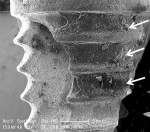

+ Minimal treatment effect = some cement removal from crest of implant threads, no cement removal from the concavities between threads (Figure 2 and Figure 3).

The CO2 9300 nm laser visibly removed most of the cement on all three implant surfaces and showed minimal surface changes under SEM (Figure 6 and Figure 7), while the Er,Cr:YSGG and Er:YAG lasers and the Nd:YAG laser alone had a minimal effect on the cement and implant surface (Figure 2 and Figure 3). Cement removal by the CO2 10,600 nm laser as a monotherapy was variable depending on the surface tested.

Table 1 reveals that none of the treatment modalities was completely successful at removing all cement from the implant test surfaces. Post-treatment SEM evaluation was carried out to obtain magnified views of residual cement and assess damage to the implant surface that might have occurred as a result of treatment. The effectiveness of cement removal varied markedly, with the implants treated with the CO2 9,300 nm laser protocol being mostly free of cement (Figure 6 and Figure 7) and the Er,Cr:YSGG and Er:YAG lasers (Figure 2 and Figure 3) and Nd:YAG laser (as a monotherapy) being minimally effective. When used as part of a dual therapy in conjunction with the piezo scaler, the Nd:YAG, CO2 10,600 nm, and diode lasers were only marginally more effective than the piezo scaler alone.